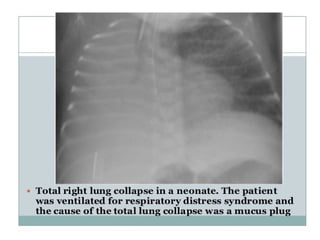

1)COMPLETE COLLAPSE • Causesopaque hemithorax with displacement of mediastinum to the affected side with compensatory hyperinflation of opposite lung often with herniation across midline. • Herniation mostly occurs in retrosternal space but may occur posterior to heart or under aortic arch